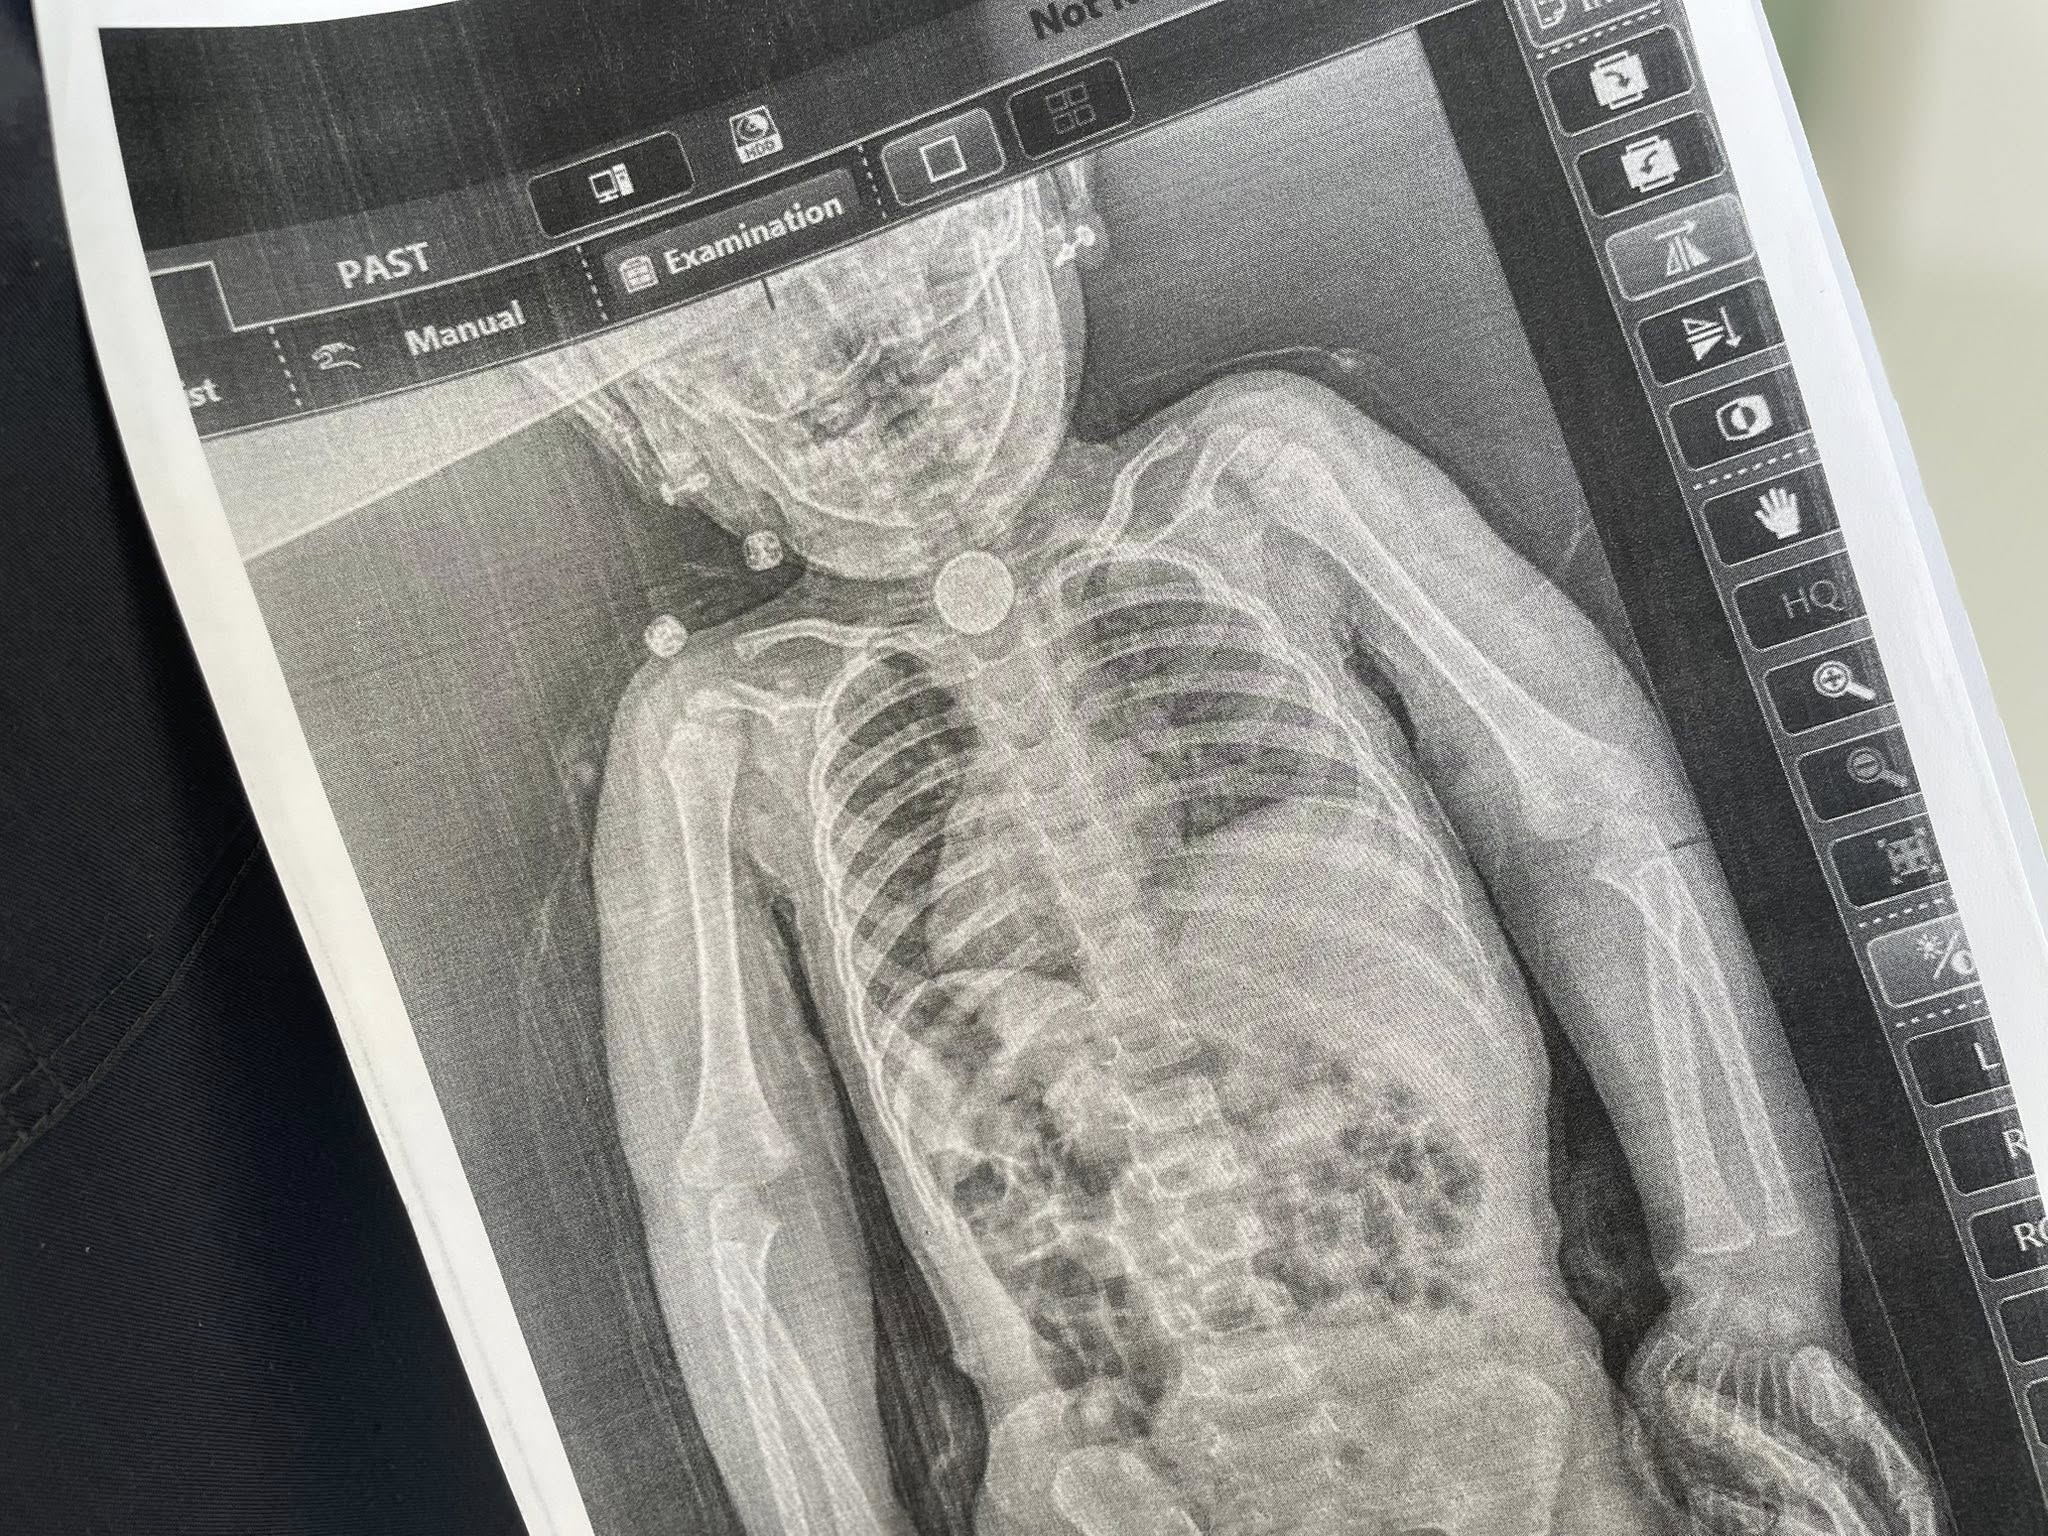

Дополнительное обследование, включая рентген, наконец показало причину – в первом физиологическом сужении пищевода прочно застряла круглая батарейка диаметром 2,5 см.

Детские хирурги провели операцию осторожно, используя ларингоскоп и специальные инструменты и успешно удалили посторонний предмет без осложнений.

Сейчас состояние девочки стабильное, однако медики продолжают следить за возможным сужением пищевода – одним из самых распространенных осложнений после длительного пребывания постороннего тела.